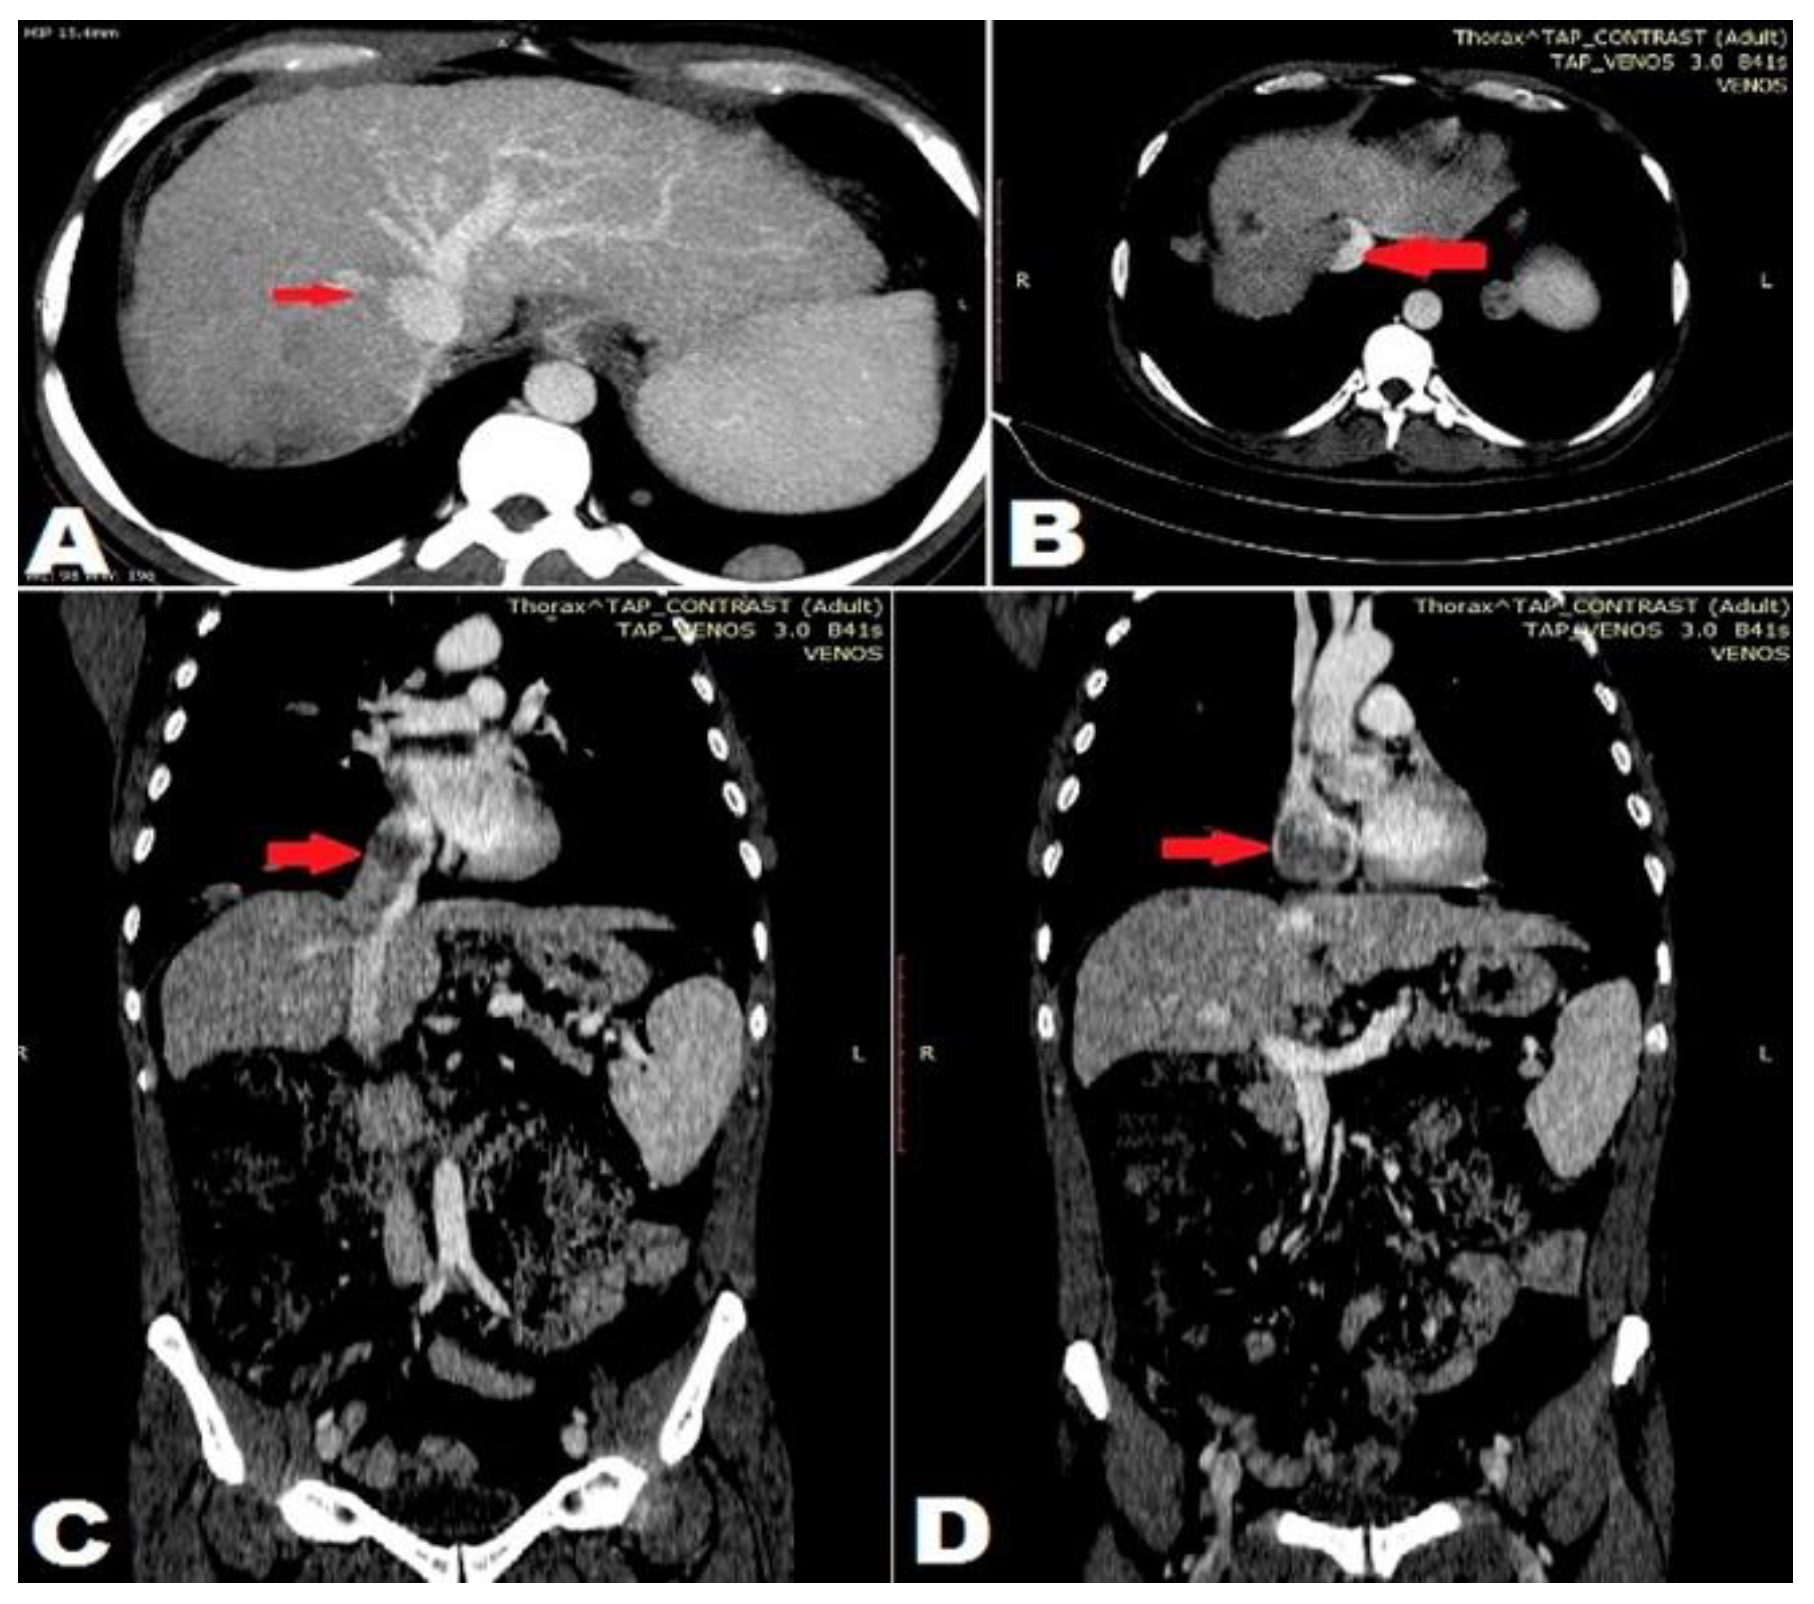

Case report